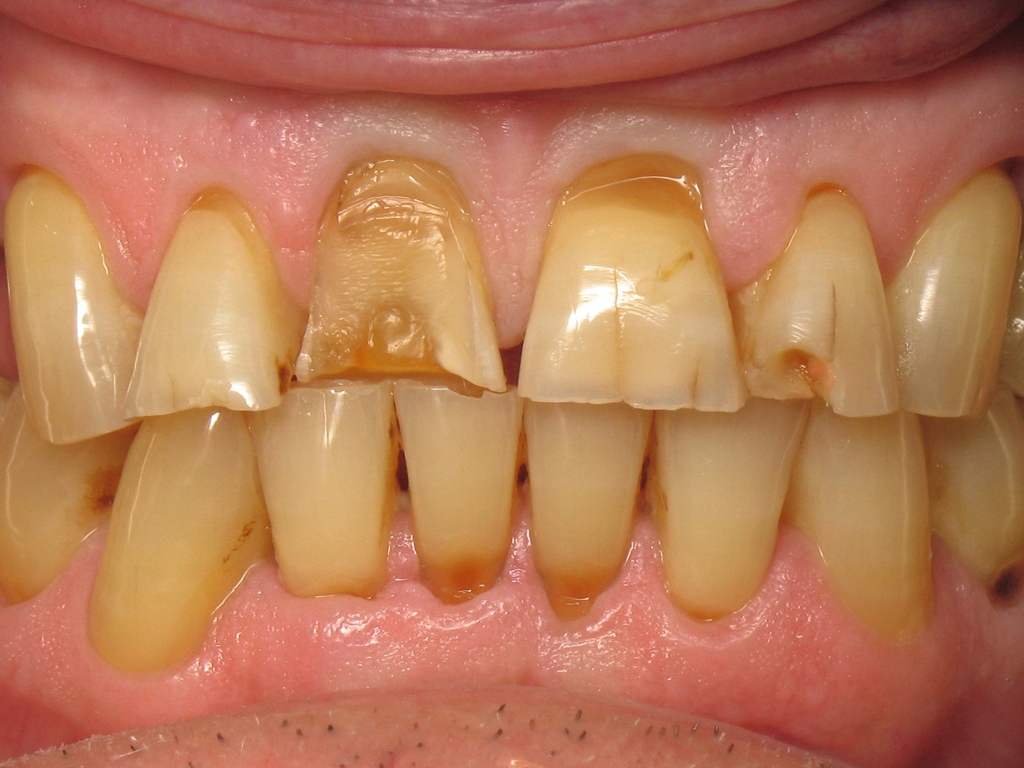

Dans le même temps, les figures 11 et 12 montrent la situation initiale de ce patient, venu en consultation pour la réhabilitation de ses incisives maxillaires. Le diagnostic a révélé un bruxisme nocturne à l’origine de plusieurs destructions coronaires : usure du bord libre, ab fraction, restaurations absentes, fêlures, et une fracture coronaire complexe. Il est aisé de comprendre pourquoi précédemment, le choix du matériau a été porte sur le zircone. Il est également facile de comprendre les motivations de ce patienta retrouver son sourire perdu. Cette dégradation par le temps est inéluctable, mais chez ce patient elle a été particulièrement rapide et agressive. Inverser le cours du temps est donc une évidence pour restaurer la santé dentaire de ce patient.

Fig. 11 : Situation initiale.

Fig. 12 : Vue rapprochée de la situation initiale